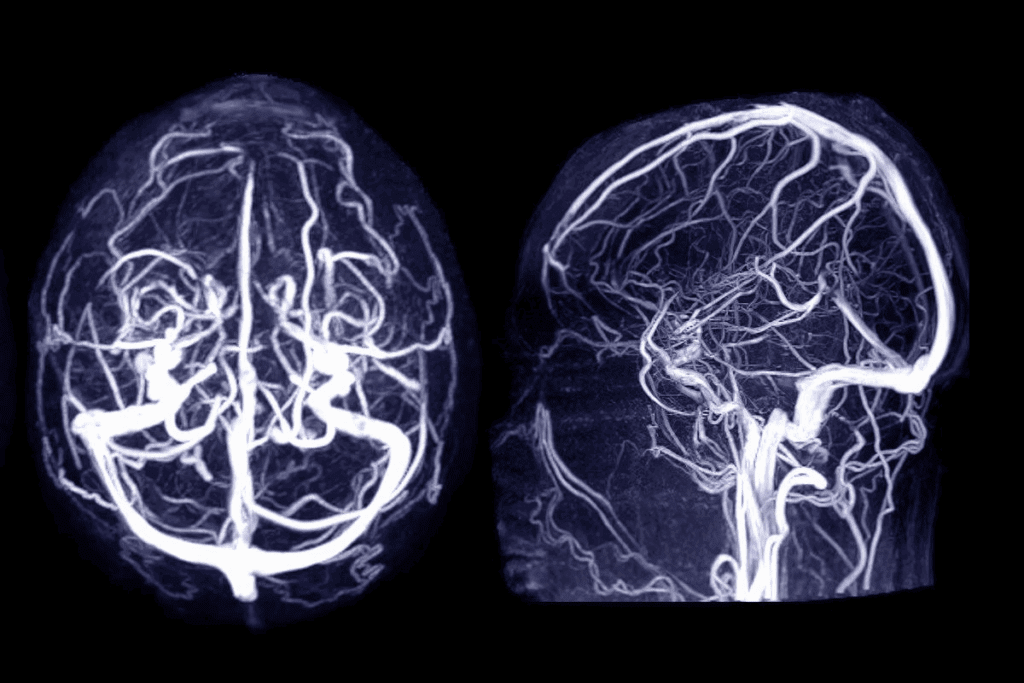

Pre-Procedure Imaging and Planning

Before starting, detailed imaging and planning are vital. We use digital subtraction angiography (DSA) and 3D rotational angiography to see the aneurysm and its surroundings. This helps us plan the best way to coil it.

Completion Angiography and Verification

After putting in coils, we do a final angiography to check if the aneurysm is closed and there are no issues. This step is key to making sure the procedure was a success and the patient is safe.